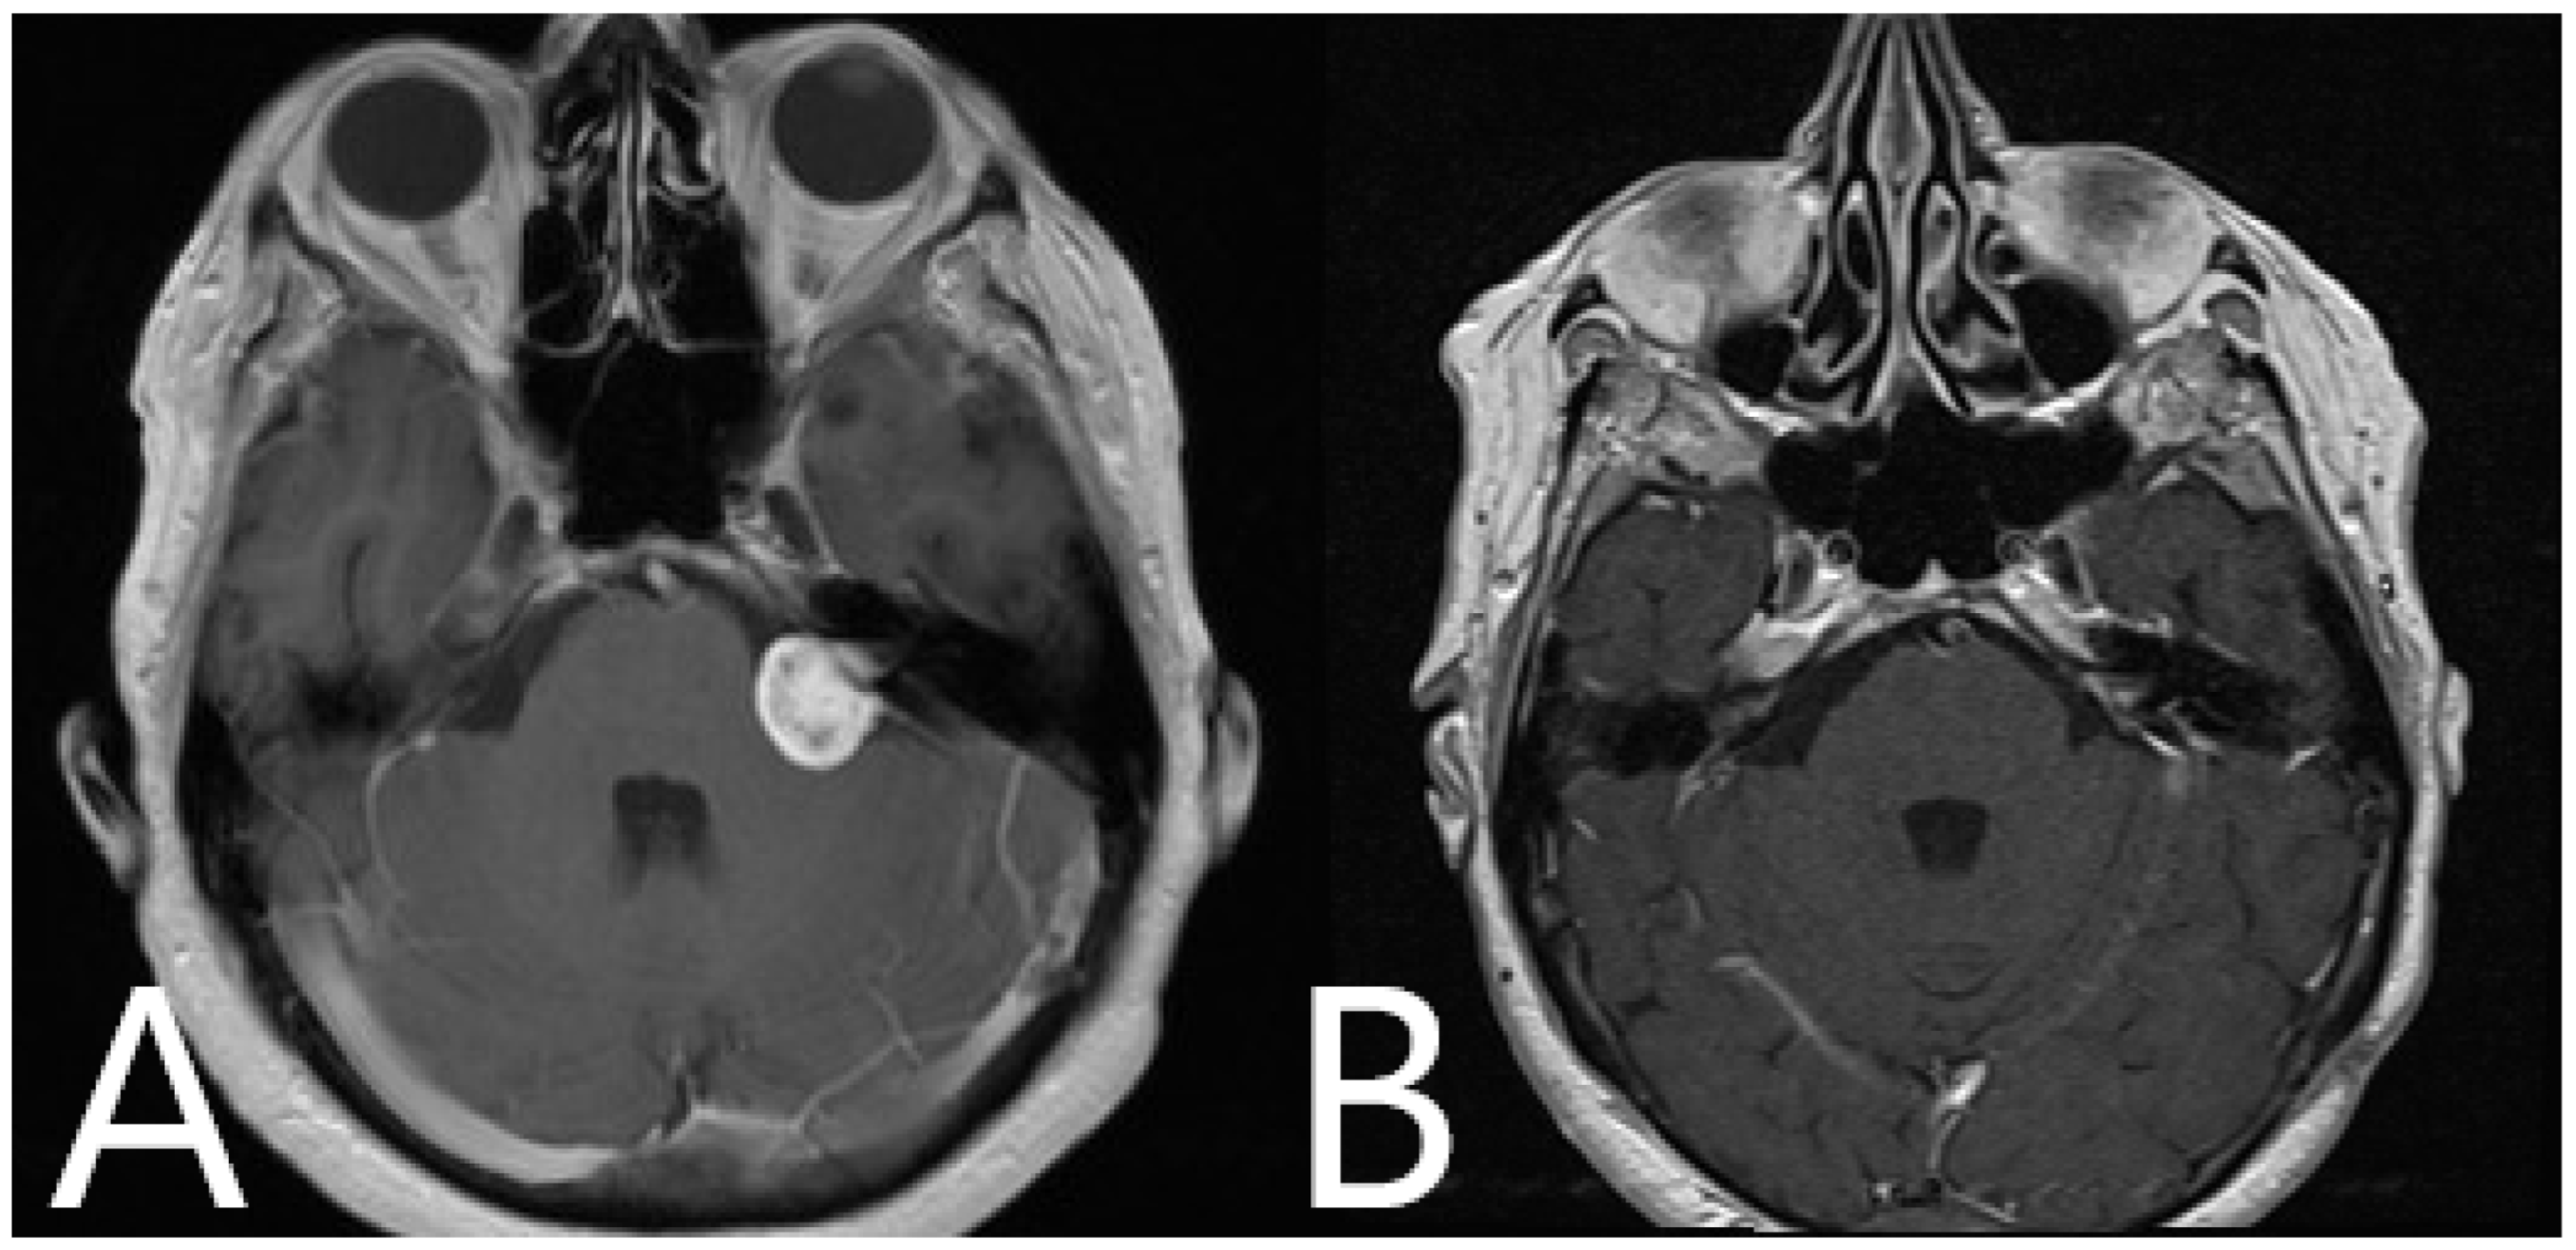

Illustrative Cases